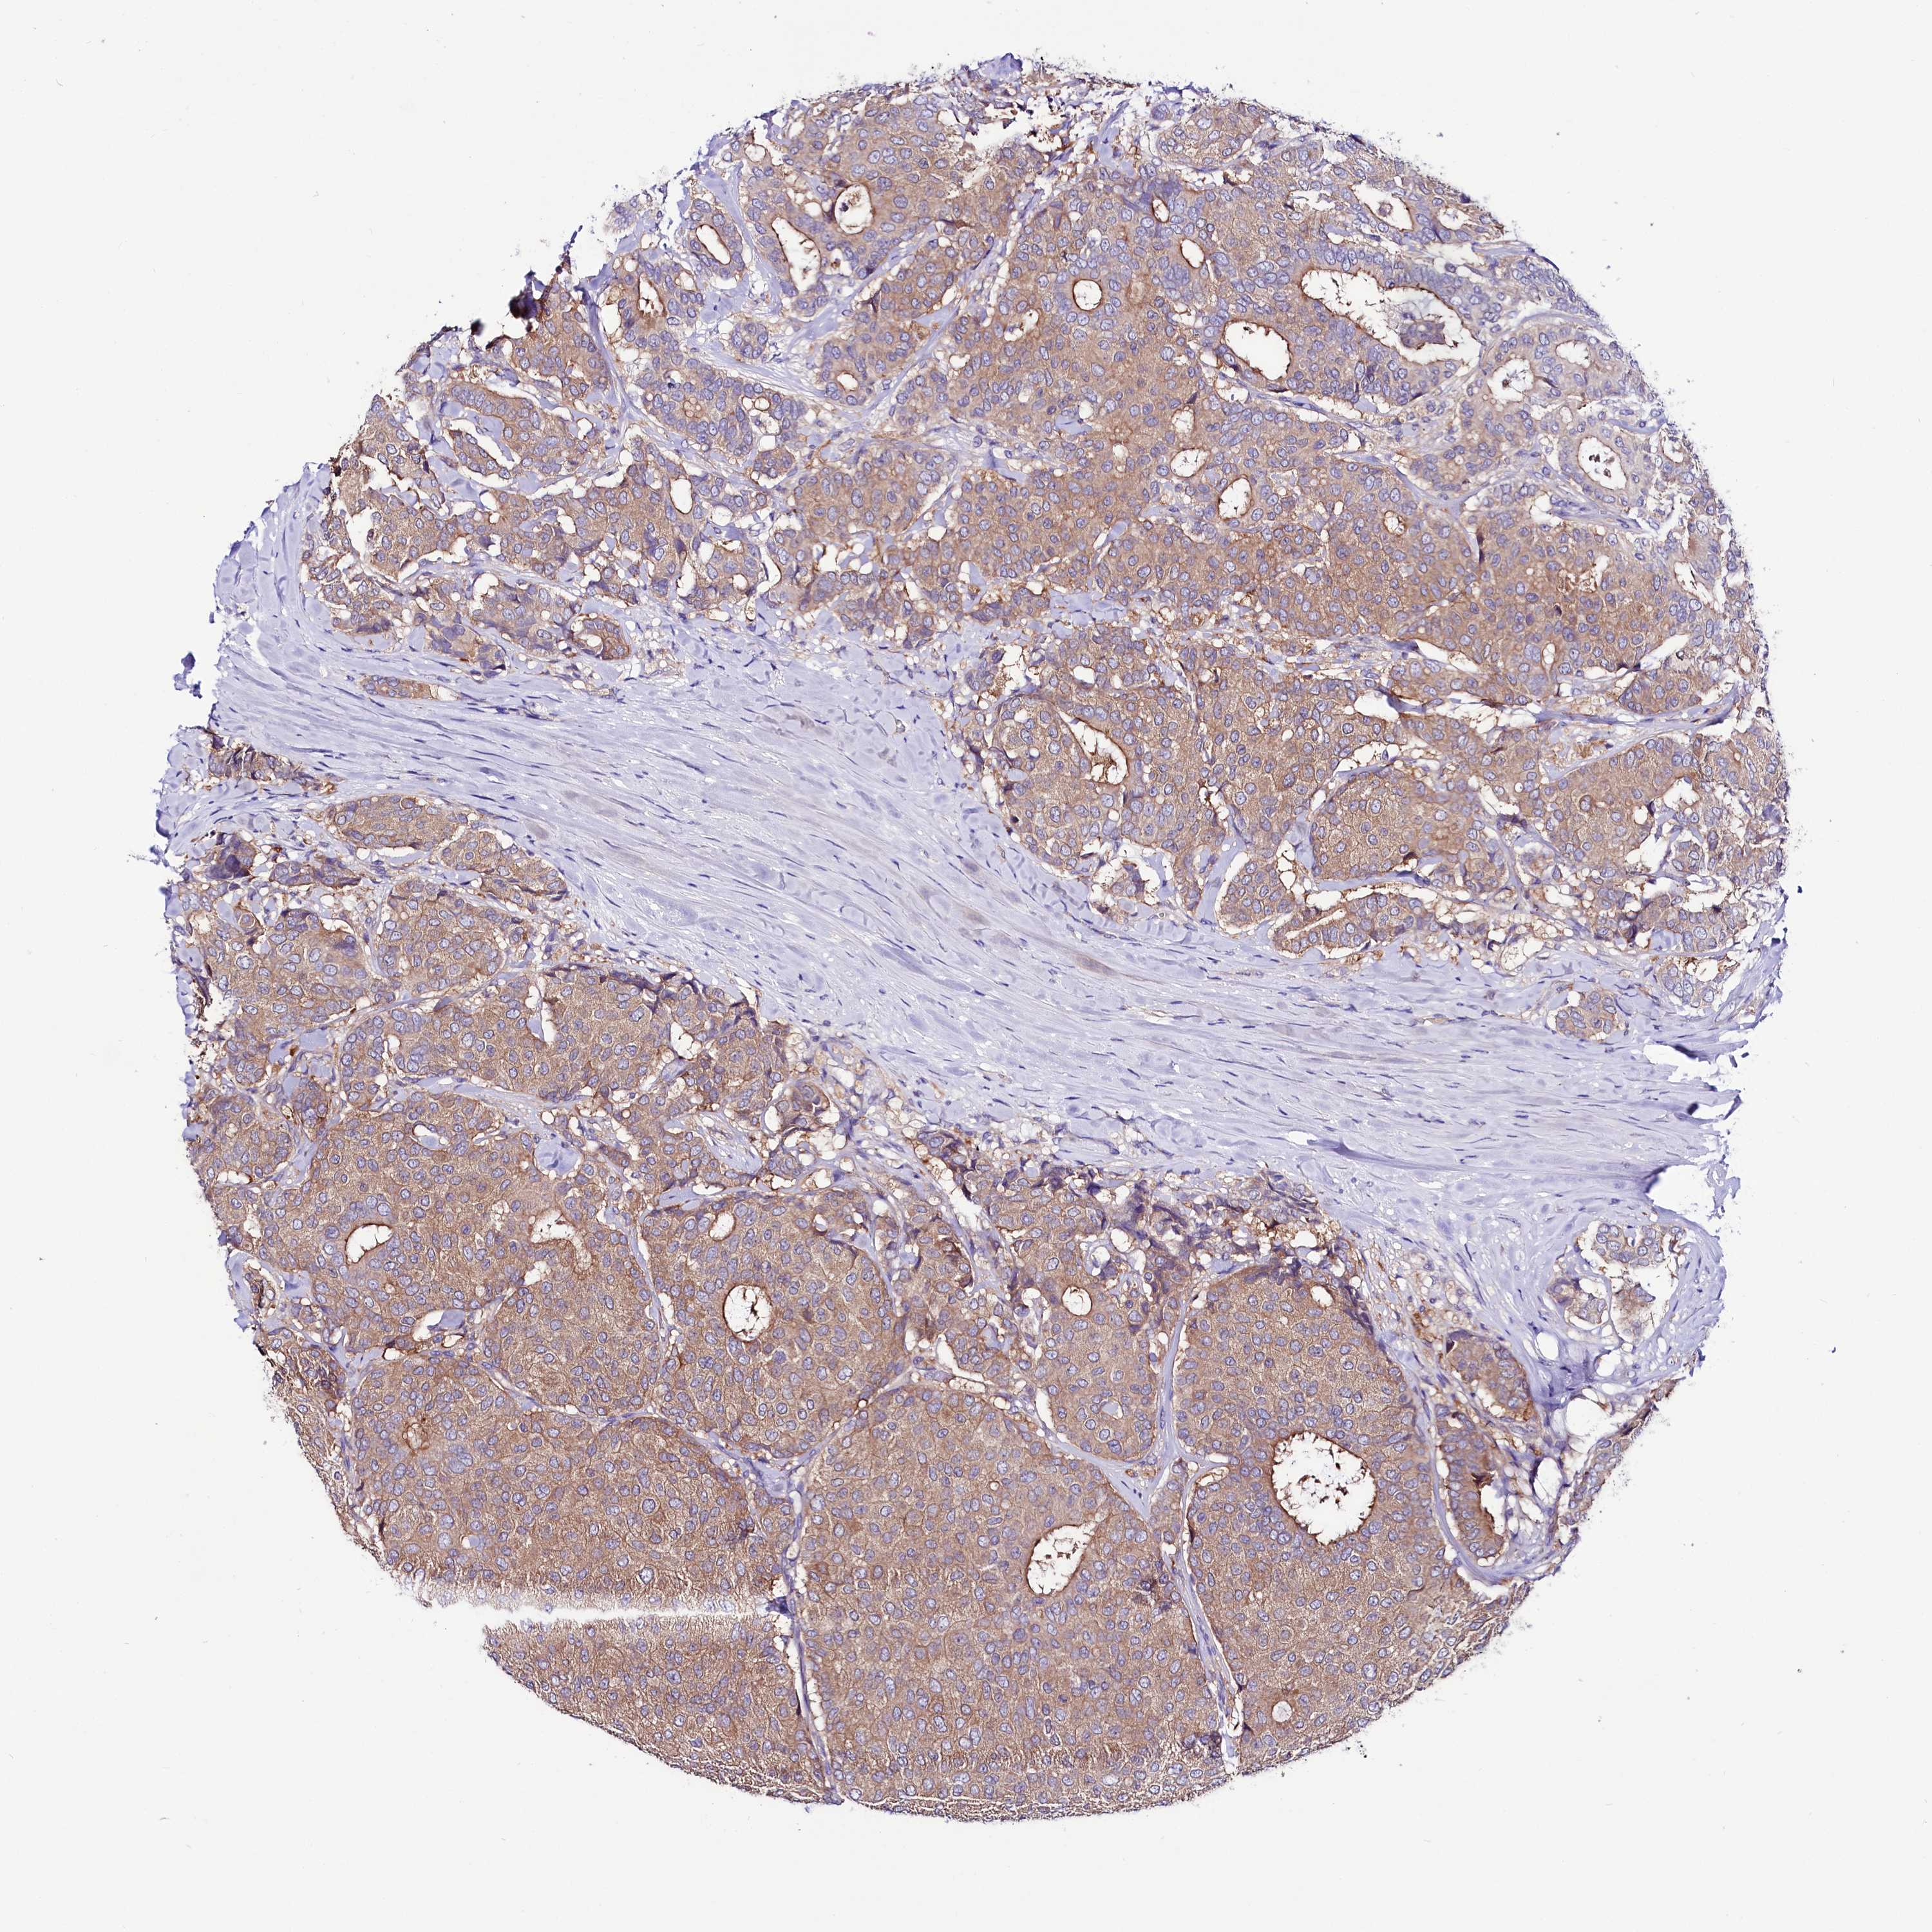

BRCA TCGA BRCA VALIDATION PROTEIN EXPRESSION

Breast cancer

Human cancer